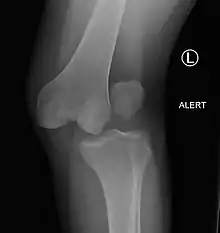

| Plain lateral X-ray of the left knee showing a posterior knee dislocation[1] | |